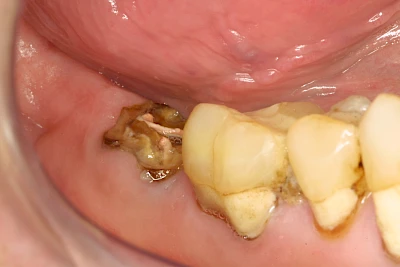

Bricht ein Zahn oder eine künstliche Zahnkrone ab, kann in der Tiefe des Zahnes Fremdmaterial zum Vorschein kommen. Wurzelkanalfüllungsmaterialien können wie "Fleischfasern" zwischen den Zähnen irritieren und sollten deshalb entfernt werden. Harte Wurzelkanal-Stifte können scharfkantig sein und die umliegenden Weichteile verletzen.